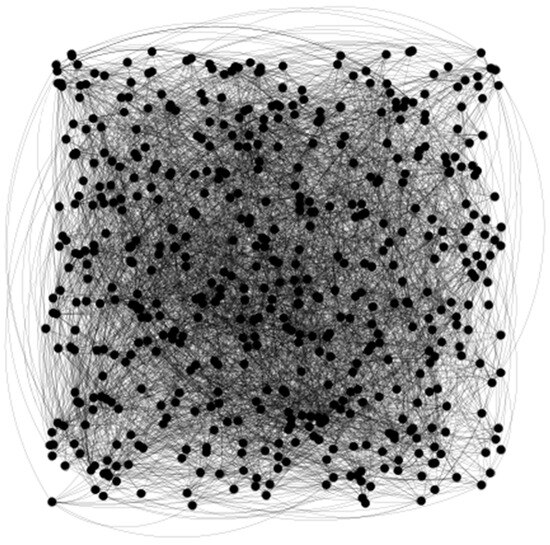

After graph construction, we partly obtained a corresponding graph (see Figure 4).

The graph construction method as well as the topological characteristics and physical characteristics have been obtained as in [16].

Figure 4. Partial graph construction. The topological characteristics of the multi-order network, combined with physical characteristics, were fused as a node feature vector.